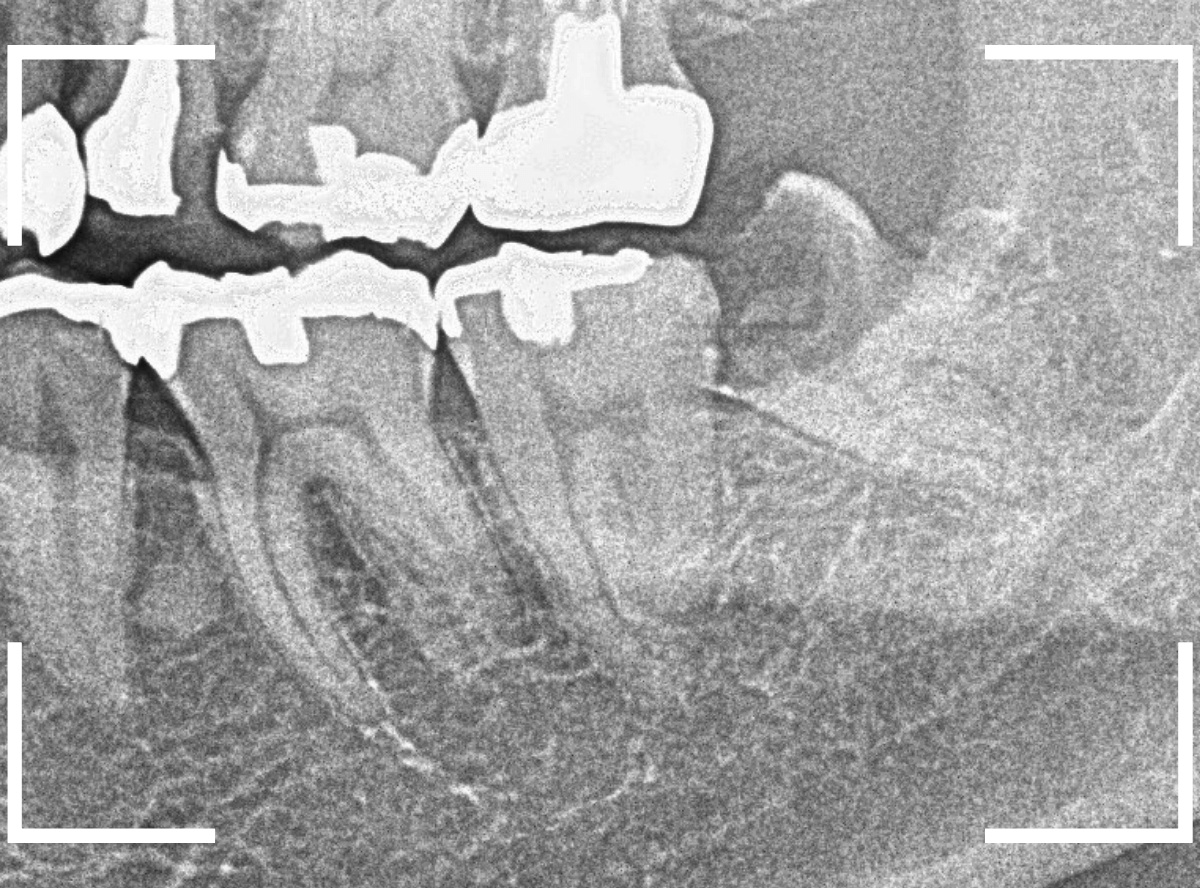

抜歯後に長期間お痛みが出たり、経過観察が必要な難しいおやしらずの抜歯ならまだしも、簡単なおやしらずの抜歯を避けてしまったがために、他の歯に悪影響を与えてしまったもったいない例も多々見てきました。

ここでは、比較的簡単なおやしらずの抜歯の例を中心にご紹介します。